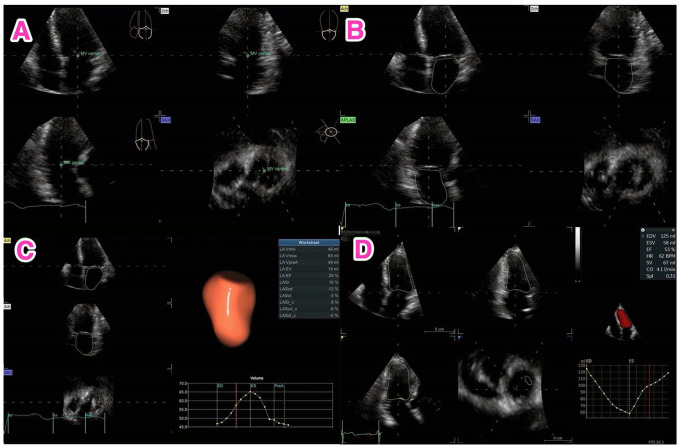

Background: Atrial fibrillation (AF) is the most common arrhythmia and can lead in the long-term to atrial remodelling. Three-dimensional speckle-tracking echocardiography allows evaluation of left atrial function and the magnitude of remodelling processes.

Methods: Echocardiography loops were collected between December 2021 and December 2022. Only valid atrial loops with sinus rhythm during examination were included. The Spearman test was used to establish correlation matrices of left atrial parameters, with uni-, multivariate and binary logistic regression to predict the presence or absence of AF.

Results: A total of 116 patients (50% females) aged 76.9 ± 11.2 years were included in the analysis. Males and females differed in anthropometric and other clinical parameters. Intra- and interobserver variability was 1.12% and 1.85%, respectively. 2D and 3D left atrial volumes correlated significantly (r = .8, P<.0001). Almost all left atrium strain measurements uni- and multivariately predicted the presence of AF, binary logistic regression model identified 2 independent parameters, left atrial longitudinal strain reservoir (LASr, P = .042) and LAS conduit phase (P = .044). LASr was significantly greater in patients without a history of AF than in patient with a history of AF (16 ± 16 and 10.5 ± 7.1, respectively; P = .012). LASr was able to discriminate between a history of paroxysmal AF and its absence with 72% specificity and 68% sensitivity with a cut-off value of 14% (AUC 0.72, 95% CI 0.62-0.82, P < .0001).

Conclusions: Three-dimensional left atrial reservoir function can differentiate patients with paroxysmal AF from patients without a history of this arrhythmia.